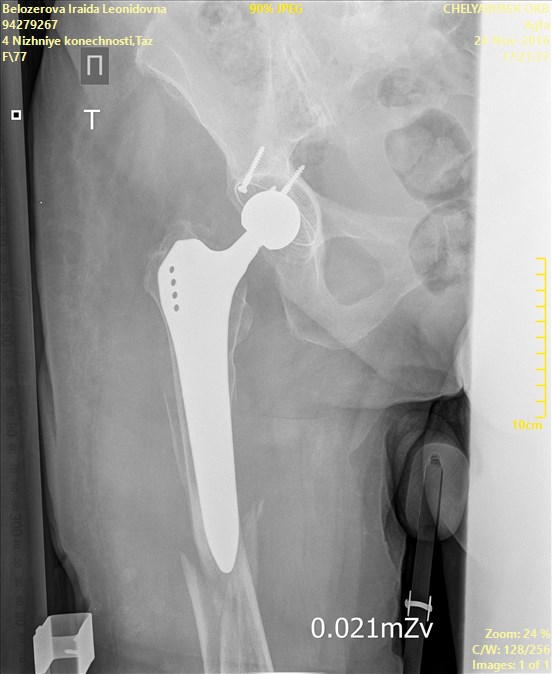

ÎÏÖËÁ   ó÷î   10(ã×ÁÊÍÀÌÌÅÒ)íÁÔÉÓ.   ðÏ   ÎÁÛÉÍ   ÉÚÍÅÒÅÎÉÑÍ  ÏÔ

ÍÅÖÍÙÝÅÌËÏ×ÏÊ ×ÙÒÅÚËÉ ÄÏ ËÏÎÃÁ ÎÏÖËÉ 204ÍÍ. îÏÇÁ ÐÒÁ×ÁÑ

Name: Belozerova_Iraida_Leonidovna_BEDRENNAYA_AP_CR(1).jpg